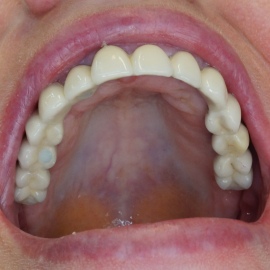

Bezzębie całkowite górne. Początkowo wykonane na mieście mosty całoceramiczne wydawały sie sukcesem, ale po roku pojawiły sie obrzęki i krwawienie z dziąseł. Pacjentka zgłosiła się do leczenia. Usunięto wszystkie zęby w szczęce. Sterowana regeneracja tkanek kości wyrostka, modelowanie kształtu i objętości tkanek miękkich, mosty porcelanowe przykręcane do implantów. Zadowalający wynik anatomiczny i estetyczny.